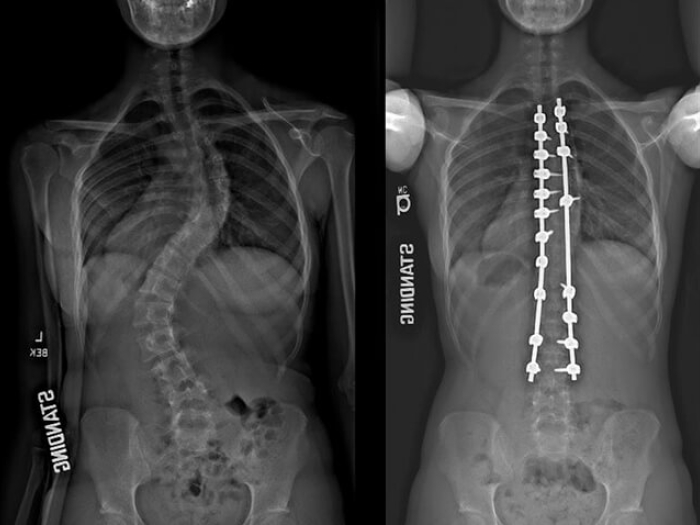

Xray image comparison of spine.